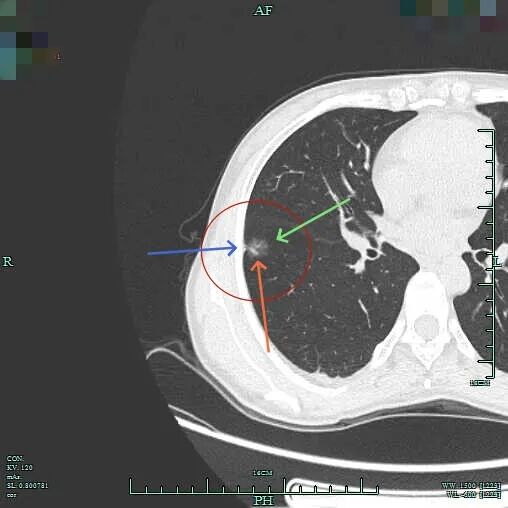

非薄层上右下主病灶A有微小血管进入,距离胸膜近,表面不平,灶内密度稍不均。

薄层上病灶出现,靠叶间裂处密度高呈实性成分,边上是磨玻璃成分,轮廓较清。

病灶处叶间裂密度较高,灶内有条状偏高密度,磨玻璃成分较淡。

灶内密度欠均匀,紧贴叶间裂,部分边缘略毛糙,整体轮廓清楚。